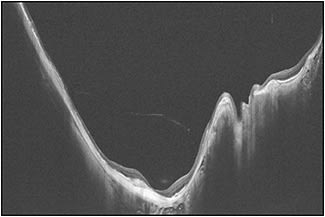

The most common methods to detect staphylomas have been color fundus photography and ultrasonography. Especially, conventional 50° fundus photos are widely used in many epidemiological studies. However, most staphylomas involve wide areas of the fundus (especially the upper and temporal direction), and thus the entire extent of the staphyloma does not fit within the 50° field of view of conventional fundus photographs (Figure 2). Similarly, in most cases, staphylomas are too wide to fit into the length of an OCT scan (Figure 3).

To solve these issues, we are conducting ongoing studies using a prototype ultra-widefield OCT by Canon Inc. (Tokyo) in our institute. In the near future, this technique will become a cost-effective and more available tool to evaluate the presence and types of staphyloma. Different from 3D MRI, widefield OCT can also visualize how the retina and optic nerve are damaged by eye deformity (Figure 5). This is important because it can demonstrate the exact cause of vision-threatening complications in pathologic myopia.